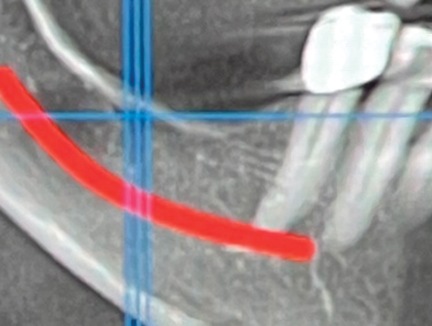

Fig 1. Implant planning and mandibular canal indicated in CBCT.

Figure 1

Patient 1 was a 69-year-old man who was a former professional athlete. He developed heart issues, which led to the use of various medications, such as metoprolol, Ventolin, Seretide, pantoprazole, Rhinocort, and Eliquis. Based on a CBCT scan (Figure 1), the patient needed augmentation in the mandibular left jaw (Siebert class I). Radiographic examination revealed a periapical lesion present at site No. 20 as well as a very thin ridge width of only 3.7 mm in the posterior mandible. Implant planning was performed using planning software, and a custom-made titanium mesh was designed (Figure 2).12